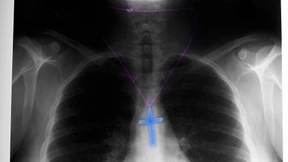

Im Frankfurter Waldstadion herrscht festliche Stimmung, doch es geht nicht um Fußball. Zehntausende Zeugen Jehovas feiern ihren Sommerkongress – und ein Jubiläum. Da dürfen Taufen im Pool nicht fehlen.